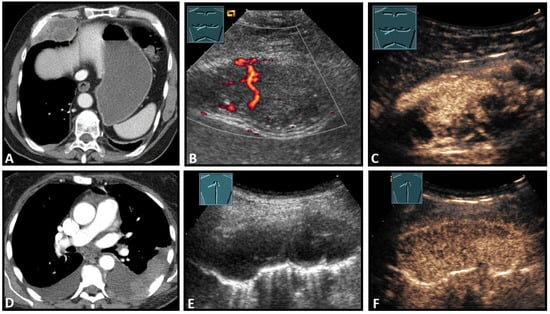

Figure 8.

Top row: a neuroendocrine tumor on computed tomography (CT) (provided by Prof. Dr. Andreas H. Mahnken, Marburg, Germany) (A), CDS (B), and CEUS (C), here with inhomogeneous enhancement. Bottom row: a plasmocytoma infiltration on CT (D), B-Mode US (E), and CEUS (F), here with homogeneous marked enhancement.